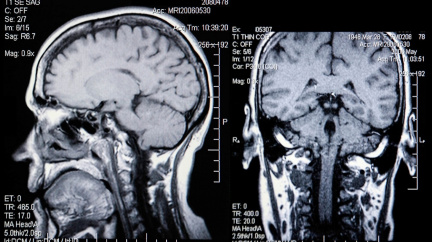

Konstatovat, že má člověk na svůj tělesný rámec neobvykle velký mozek, by bylo hrubé podcenění skutečného stavu věcí. Dokonce i na poměry primátů je centrum naší nervové soustavy skutečně obrovské – v průměru tvoří asi dvě procenta hmotnosti lidského těla. Ba co víc, na energetické spotřebě se podílí až z jedné pětiny.